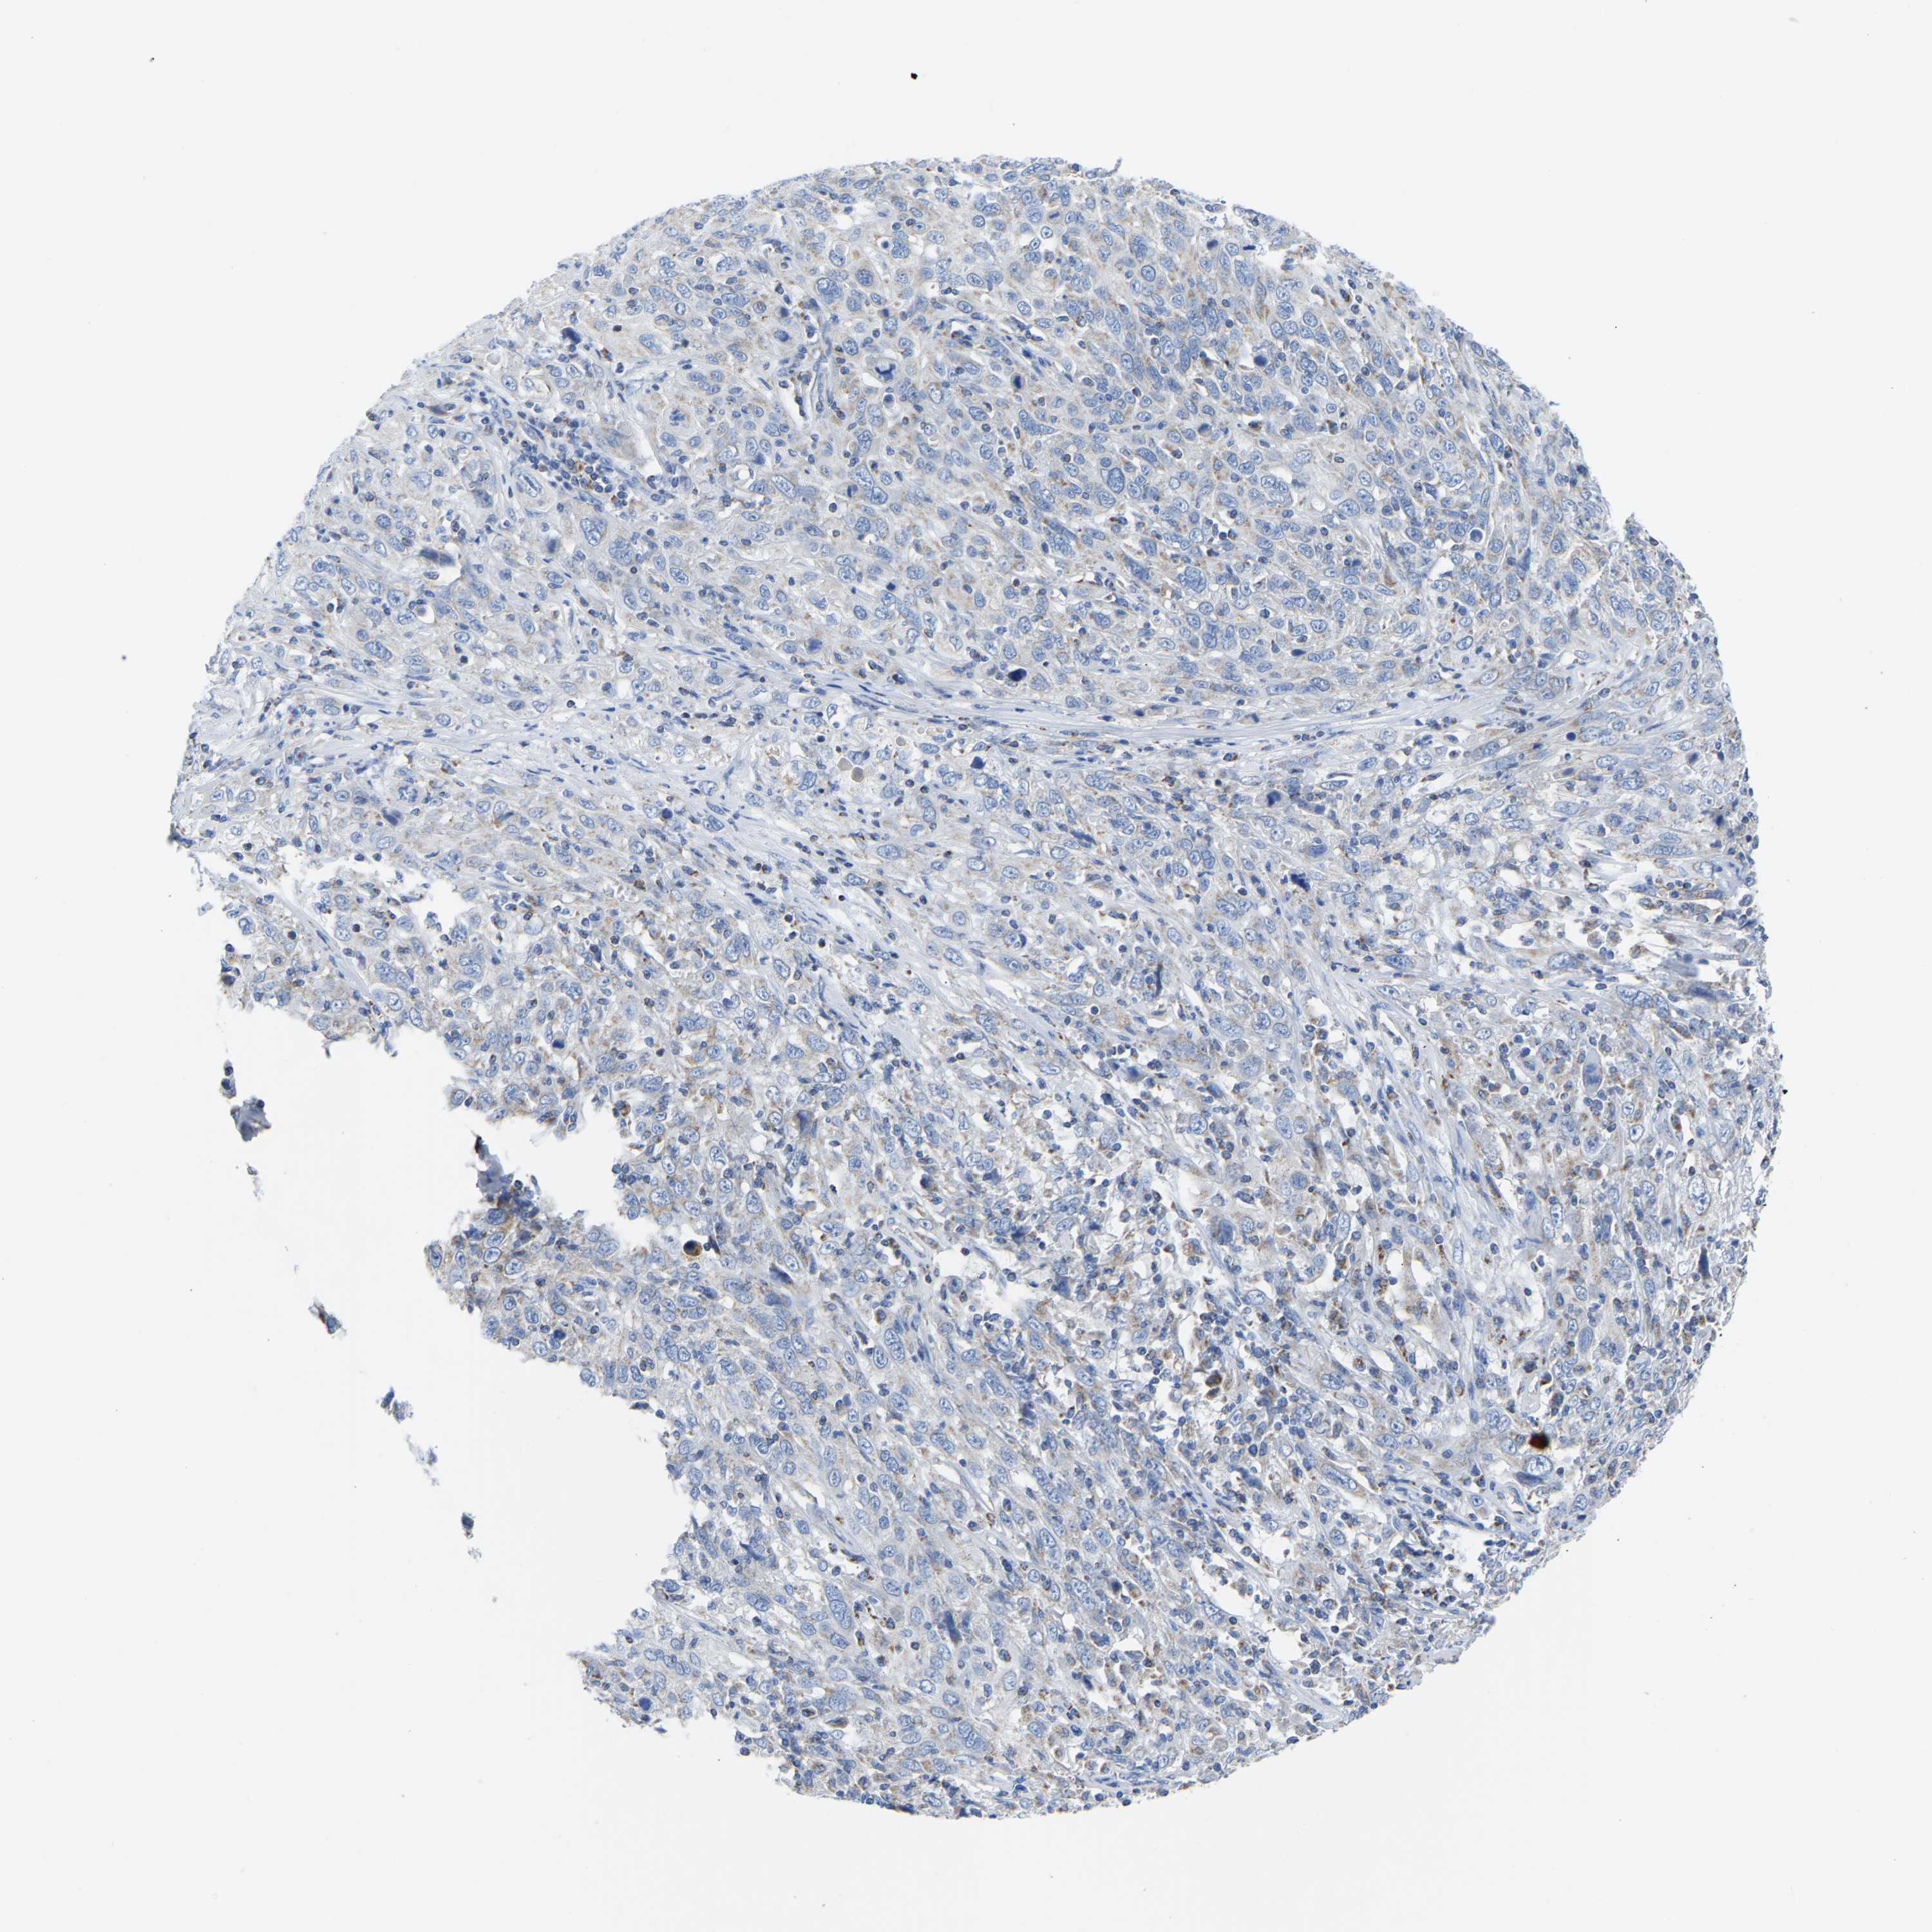

CERVICAL CANCER - Protein expressioni

A mouse-over function shows sample information and annotation data. Click on an image to view it in a full screen mode. Samples can be filtered based on level of antibody staining by selecting one or several of the following categories: high, medium, low and not detected. The assay and annotation is described here.

Note that samples used for immunohistochemistry by the Human Protein Atlas do not correspond to samples in the TCGA dataset.

Antibody stainingi

Antibody staining in the annotated cell types in the current human tissue is reported as not detected, low, medium, or high, based on conventional immunohistochemistry profiling in selected tissues. This score is based on the combination of the staining intensity and fraction of stained cells.

Each image is clickable and will lead to virtual microscopy that enables deeper exploration of all samples and also displays staining intensity scores, fraction scores and subcellular localization as well as patient and tissue information for each sample.

Antibody HPA018990

Squamous cell carcinoma, NOS